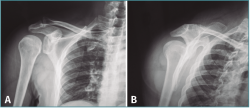

A la exploración física presenta dolor intenso a la palpación e impotencia funcional en el hombro, sin deformidad evidente y con bloqueo de los movimientos rotacionales. Tras realizar radiografías simples en proyecciones anteroposterior e “Y” de escápula (Figura 1), se diagnostica de luxación posterior de hombro.

Figura 1. Radiografía anteroposterior (AP) (A) y proyección en “Y” de escápula (B) donde se objetiva una luxación glenohumeral posterior. En la proyección AP podemos apreciar el clásico signo de la bombilla (light-bulb sign) debido a la rotación interna del brazo.